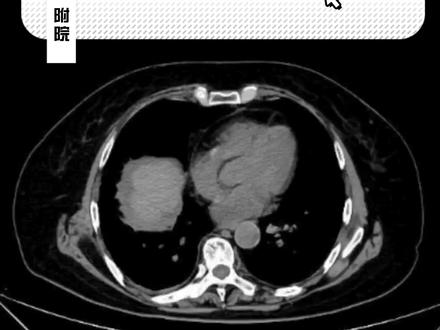

你好你好,他这个患者哈就是反面典型血糖控制不好,他这次发烧跟糖尿病控制不好非常有关系。这个患者来的时候是一个发烧的病人,在急诊诊断不清楚,发烧好几天 得不到控制,持续高热,肺 ct 当时没有很大问题,但是腹部查的也没有什么问题,就是发热原因不清楚。他有一个非常典型的慢性病史,就是糖尿病 发热待查,也是个感染性疾病,也是个发热,所以就送到我们科儿了。送到我们科儿在排查的过程中就发现 肝脏有这个肝脓肿,肝脓肿和这个糖尿病经常会有这种联系,尤其血糖控制不好的,这种病出现的肝脏的一个继发感染。这种肝脓肿处理起来难度比较大,如果是早期弥散的炎症性改变,仅仅需要抗炎治疗,就用 抗生素,到后期的时候出现脓肿,出现液化,出现脓包的时候就可以进行穿刺引流,这时候穿刺就比较容易一些。他现在这种肝脏这种感染还没有完全液化,所以没法进行穿刺, 只能进行这个抗盐治疗,药物治疗。但他这个经过这段时间抗盐之后,虽说也有发烧,但比来的时候要强,那时候持续高热,体温很高很高,血象也高,降血压,但是现在化验指标逐渐逐渐往下降,但是没有完全控制,这就没有液化,就像脓包似的, 脓包液化之后一穿刺脓方出来就好,但没有液化是一个种,穿也没有用,穿不出来他还差点火候,等什么时候这个脓肿熟了,里面形成液化了,形成脓肿了,这时候咱们后续穿刺,这样处理血会更好一些。 你别紧张,咱家人条件不是很好,也是个低保,但是没有办法,这种病人出现了,咱也有尽努力去给他处理嘛。老妈照顾孩子,你儿多大岁数?五十八岁,五十八岁,这老妈九十岁, 天天照顾孩子,你挺不容易也挺难的,咱都能理解,咱都一起努力吧,你也多保重身体。九十岁人了,我每次看你吧我都觉得心疼。照顾儿子也不容易,孩子还上班,晚上打打,班完白天自己去干活去。现在吧,一个是经济条件不是很好, 再一个家里没有人手,这也是个问题。孩子少,像过去的孩子,一堆孩子哈,四五个孩子每人搭一半天班也够用。家里没有人,所以住院经常会遇到这种情况。就是这个没有人照顾,让老妈照顾也挺不容易,所以咱坚持吧,咱咱都得坚持。